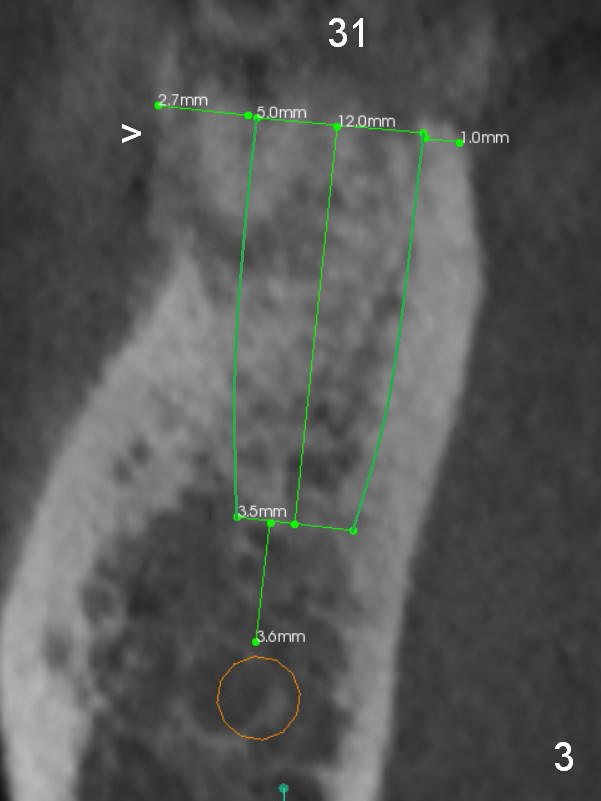

A 47-year-old woman has had 3 bridges. One of them (the lower right) is broken down. The patient requests removing the tooth #31 (Fig.1 CBCT), because of difficulty in keeping it clean. Since the buccal plate is thin (Fig.2 (axial section), 3 (coronal section) >) or absent (Fig.2 *), a 5 mm implant will be placed lingually (Clindamycin). Tap will be used prior to implant placement.